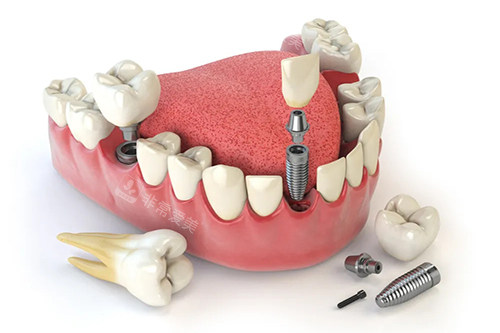

例如,对于牙齿缺失患者,提供多种种植牙方案供选择,包括不同品牌的种植体,以满足不同患者的经济和功能需求;对于牙齿矫正,采用靠前的隐形矫正技术,既美观又舒适。